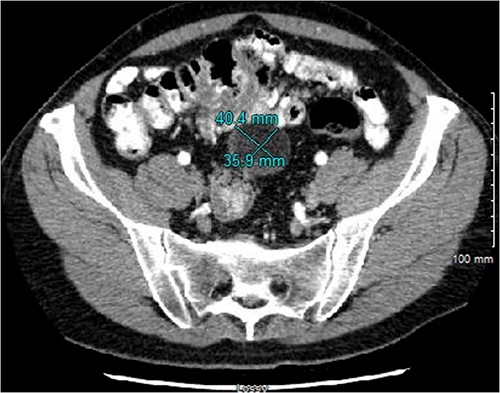

The patient underwent serial cross-sectional imaging that demonstrated stable appearance of the mass with migration of the redundant cecum and associated mass into the pelvis (Fig. 2). Colonoscopy showed a normal cecal base and no concerning features apart from sigmoid colon polyps. Due to the location, percutaneous biopsy was considered but ultimately was non-feasible due to anatomic constraints.

CT imaging from 4 months after initial diagnosis, showing a 4.0 × 3.6 × 3.8 cm, seemingly lipomatous mass in the midpelvis.